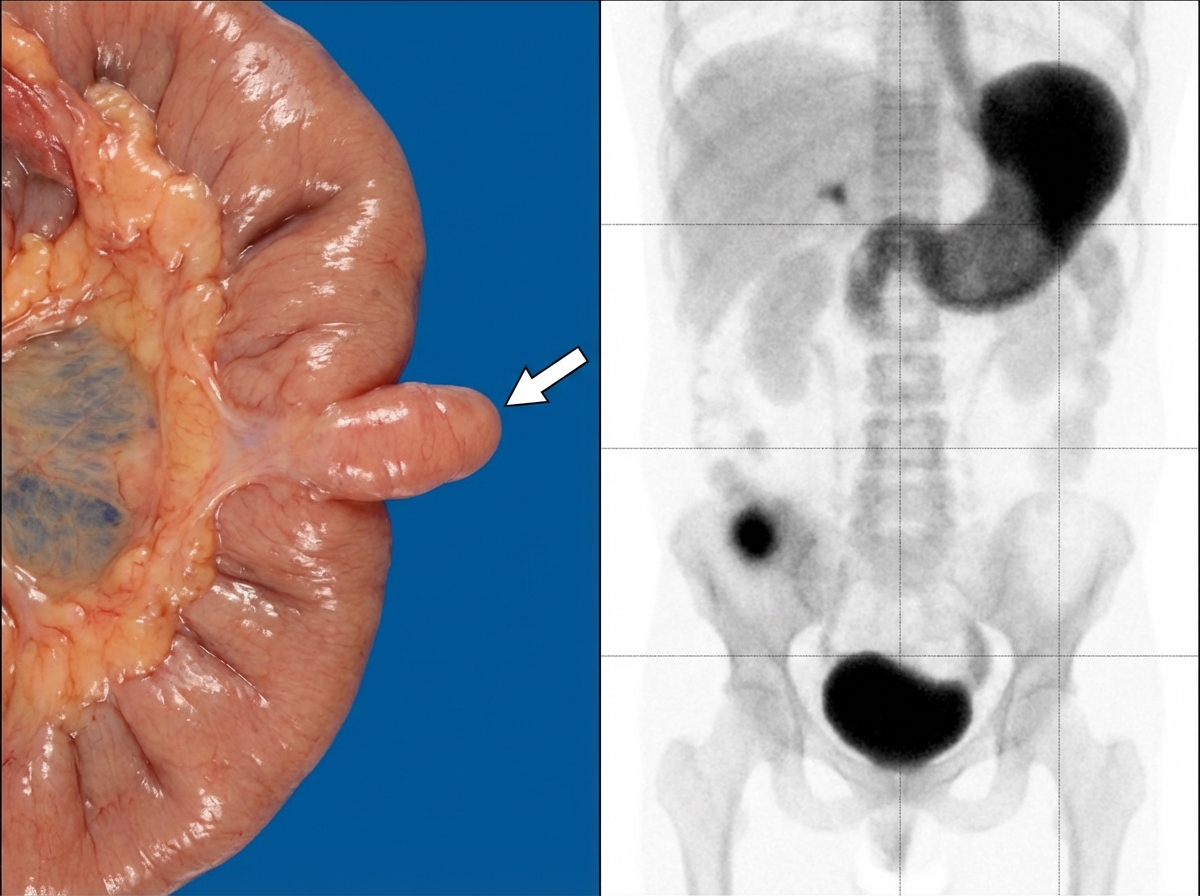

The following image shows \qquad and the test being performed is \qquad ?

Explanation: ***Meckel's Diverticulum, Technetium scan*** - The image on the left shows a **true diverticulum** of the small intestine, consistent with a **Meckel's diverticulum**, which is a remnant of the vitelline duct. The arrow indicates the diverticulum. - The images on the right show a **Technetium-99m pertechnetate scan**, demonstrating focal uptake (indicated by the arrows) in the lower abdomen, consistent with **ectopic gastric mucosa** typically found in a Meckel's diverticulum. *Carcinoid Tumor, Octreo-scan* - A **carcinoid tumor** is a neuroendocrine tumor, and while it can occur in the small bowel, its appearance on gross examination would be different from the diverticulum shown. - An **OctreoScan** (using somatostatin analogs) is used to detect neuroendocrine tumors like carcinoids due to their somatostatin receptors, but the scan image does not show a pattern consistent with this. *Extra-adrenal Pheochromocytoma, PET DOPA scan* - An **extra-adrenal pheochromocytoma** is a tumor of chromaffin cells outside the adrenal gland, and it would not appear as an intestinal diverticulum. - A **PET DOPA scan** (using 18F-DOPA) is used to localize pheochromocytomas, but the imaging pattern shown is not characteristic of this type of scan for such a tumor. *Adrenal Pheochromocytoma, MIBG scan* - An **adrenal pheochromocytoma** is a tumor of the adrenal gland, which is located in the retroperitoneum, completely distinct from the intestinal structure shown on the left. - An **MIBG scan** (using meta-iodobenzylguanidine) is used to localize pheochromocytomas because MIBG is selectively taken up by chromaffin cells, but the images do not represent an MIBG scan or an adrenal pathology. *Intestinal Lymphoma, PET-CT scan* - **Intestinal lymphoma** can occur in the small bowel but would typically present as a mass lesion or infiltrative process, not as an isolated diverticulum. - A **PET-CT scan** using fluorodeoxyglucose (FDG) is used for staging and evaluating lymphoma due to increased glucose metabolism in malignant cells, but the imaging pattern shown does not demonstrate the diffuse FDG uptake characteristic of PET-CT.

Explanation: ***Broad-base of this defect should be amputated at its base*** - This statement is incorrect. While a broad-based diverticulum (like Meckel's diverticulum shown) may require surgical resection, it should not be simply amputated at its base. Resection should involve removing the diverticulum along with a small segment of the adjacent ileum to reduce the risk of recurrence or complications due to heterotopic mucosa. - Simple amputation at a broad base can lead to **retained heterotopic mucosa**, increasing the risk of subsequent complications such as ulceration, bleeding, or perforation. *It is remnant of vitello intestinal duct* - This statement is correct. The image displays a **Meckel's diverticulum**, which is a **true diverticulum** representing a persistent portion of the embryonic **vitelline duct** (also known as the omphalomesenteric duct). - This duct normally connects the developing midgut to the yolk sac during fetal development and typically obliterates by the seventh week of gestation. *This condition can be a lead point for ileoileal or ileocolic intussusception* - This statement is correct. A Meckel's diverticulum can act as a **lead point** for **intussusception**, where one segment of the intestine telescopes into an adjacent segment. - The diverticulum's mobility and potential for invagination make it a common cause of intussusception, especially in children, leading to bowel obstruction. *This condition is mostly asymptomatic* - This statement is correct. Meckel's diverticulum is typically **asymptomatic** in a majority of individuals who have it. - While it can cause complications like bleeding, inflammation (diverticulitis), obstruction, or perforation, these complications occur in only a small percentage of affected individuals, demonstrating its generally silent nature. *It is the most common congenital anomaly of the gastrointestinal tract* - This statement is correct. Meckel's diverticulum is indeed the **most common congenital anomaly of the gastrointestinal tract**, occurring in approximately **2% of the population**. - It follows the **"rule of 2s"**: affects 2% of population, located approximately 2 feet from the ileocecal valve, is typically 2 inches long, and only 2% become symptomatic.